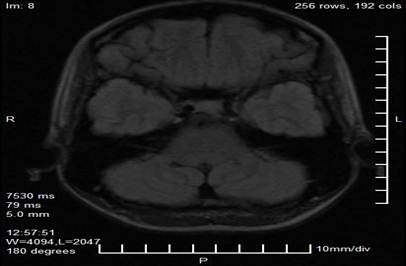

Complementary studies included a brain MRI with a neuro-ophthalmological protocol, which revealed a nodular, lobulated, well-defined image in the projection of the pineal gland, measuring 29 mm × 28 mm × 27 mm. The lesion had heterogeneous signal characteristics, with areas of hyperintensity on T1 and T2 sequences suggestive of a hemorrhagic or vascular component, and showed a compressive effect on the midbrain tectum and superior colliculi. No signs of obstructive hydrocephalus or intracranial hypertension were observed in the obtained slices (Figures 2 and 3).

Figure 2. Axial magnetic resonance imaging cut in T1 sequence showing a lobulated nodular lesion in the projection of the pineal gland (arrow), with heterogeneous hyperintensity suggestive of a hemorrhagic or vascular component.